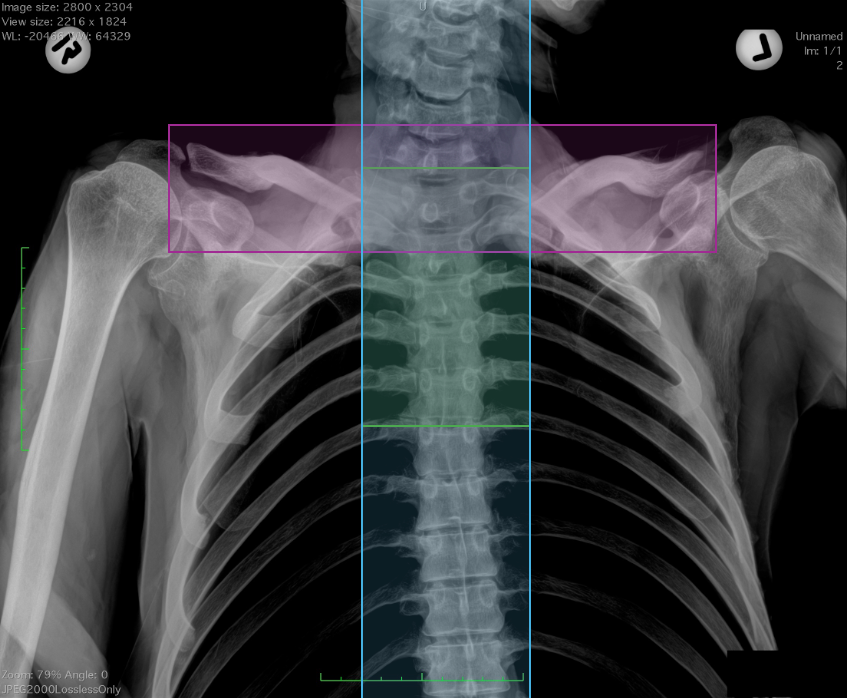

Members of the Michigan State University Forensic Anthropology Lab, including Carolyn Isaac, Todd Fenton, Joseph Hefner, and doctoral student Alexis VanBaarle, co-authored a new study which analyzed over 5,000 chest radiographs, identifying different regions of interest that aid in identifying a person. The study used deep neural networks, a type of AI program, which allow for large numbers of radiographs to be analyzed in a fraction of the time.

This AI approach is the first of its kind to evaluate how different ROIs within radiographs can be used for human identification in forensic contexts.